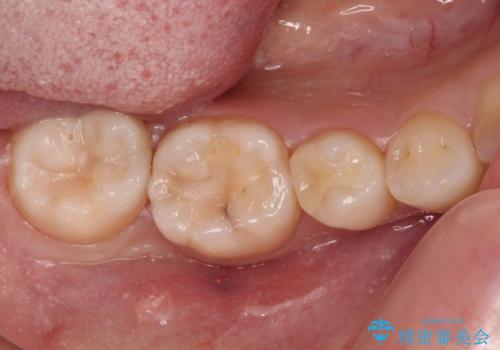

- 近々海外へ転居するとのことで、事前に処置をしておくべきむし歯がないか、気にして来院された患者様です。

レントゲン写真などから、速やかに処置を行うべき歯が2歯あったため、それぞれセラミックインレーとPGAインレー(ゴールドインレー)にて修復治療を行うこととしました。

どちらの歯も痛みなどの症状はなく、治療後も異常所見なく経過をたどっています。